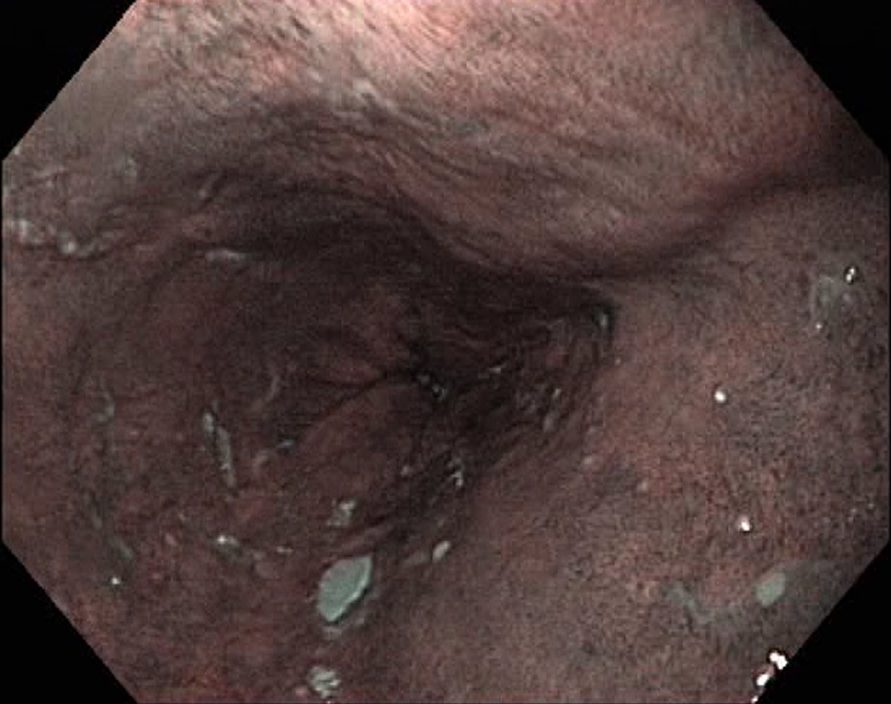

Barrets Oesophagus (NBI, Narrow Band Imaging)